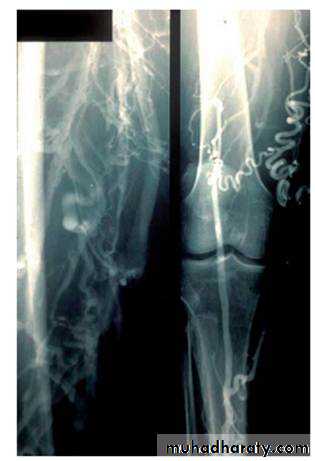

Popliteal aneurysm